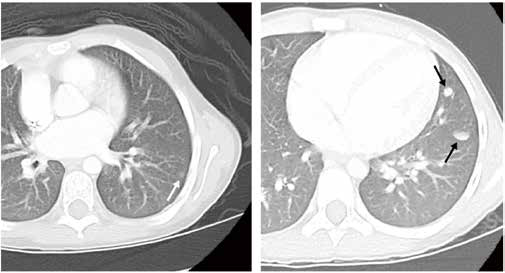

2个周期的长春新碱、放线菌素D、多柔比星(DD-4A方案)化疗后,研究者采用胸部CT评估肺结节应答情况,以确定肺结节快速完全缓解(RCR)队列和肺结节缓慢的不完全缓解(SIR)队列;在两个队列中比较肺转移数量和大小对无事件生存(EFS)和总生存(OS)的影响,其中RCR队列接受额外的DD-4A方案但不接受肺部放疗,SIR队列接受原来的三药加环磷酰胺/依托泊苷(M方案)并配合肺部放疗。